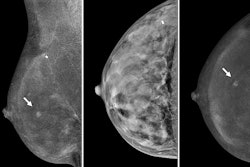

Radiologists continue to explore the potential of CEM in clinical use, with previous studies highlighting the breast imaging modality’s boosted sensitivity and specificity compared to other such imaging methods. These studies also suggest that CEM could be a useful tool in imaging dense breasts, in which standard mammography struggles to image.

Sanders and colleagues conducted a retrospective, intraindividual comparison of MGD between these three modalities, as well as a combined protocol using both DBT and full-field digital mammography in women undergoing breast cancer screening.

The final analysis included 389 women with a median age of 57.4 years who had an elevated risk of breast cancer. The women underwent breast cancer screening by combined mammography-DBT and CEM between 2019 and 2021. The team evaluated a total of 764 breasts (383 left, 381 right) and gathered MGD and BI-RADS data from DICOM metadata and radiology reports.